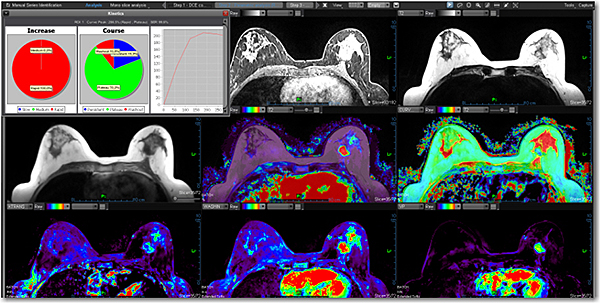

Додаток Breast Streamlined.

Додаток Breast Streamlined*- це ефективний інструмент для виявлення, характеристики та постановки діагнозу для утворень молочної залози. Цей додаток обчислює та відображає звичайні, дифузійні та кінетичні карти (якісні) та пропонує повний мультипараметричний аналіз, включаючи MPR та 3D візуалізацію, сегментацію об'єму, синтез кількох серій, кінетику та аналіз кривих. До Breast Streamlined також входить остання версія протоколу на основі BI-RADS® ATLAS. Цей пакет є корисним для поліпшення комунікації між рентгенологами, пацієнтами та направляючими лікарями. Стандартний інструмент звітності забезпечує хорошу оцінку ризику та спостереження за підозрілими знахідками.

Додаток MR Breast

Додаток Breast інтегровано у розширену візуалізацію Vitrea і забезпечує ефективні інструменти для виявлення, характеристики та стадіювання ураження молочної залози.

Забезпечує миттєву комплексну оцінку ураження та високу якість оцінки дифузії

Пропонує звітність BI-RADS® ATLAS, що полегшує комунікацію між лікарями

Пропонує два додатки:

Streamlined для стандартних протоколів

Expanded для глибокого аналізу.